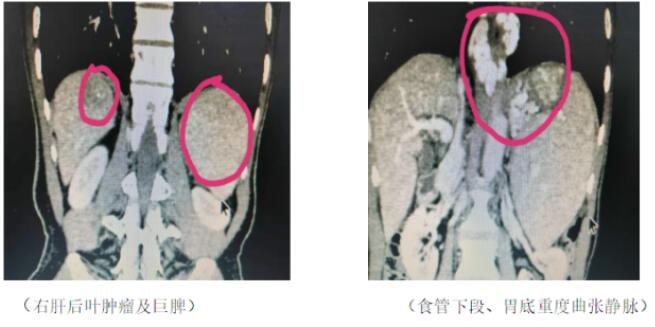

患者為一名53歲男性,因“牙齦出血1月”入院,既往半年前因“上消化道大出血”行“食管下段曲張靜脈套扎術(shù)”。完善相關(guān)檢查后診斷為:1、乙肝,丙肝,肝炎后肝硬化,右肝后葉(VII段)腫瘤;2、門靜脈高壓癥,脾亢,巨脾,白細(xì)胞減少,血小板減少,食管下段、胃底靜脈重度曲張。該名患者肝腫瘤位于右肝后葉(VII段),位置較深且隱蔽,非常不好暴露;門靜脈高壓癥病人,腹腔內(nèi)曲張血管叢非常多,靜脈壁薄易出血,稍有不慎,就會(huì)腹腔大出血危及病人生命。經(jīng)過科室討論,認(rèn)為該手術(shù)非常復(fù)雜、難度大、風(fēng)險(xiǎn)高,極具挑戰(zhàn)性。

2020年1月9日,在麻醉科及手術(shù)室護(hù)士團(tuán)隊(duì)的配合下,手術(shù)團(tuán)隊(duì)精心操作,克服艱難險(xiǎn)阻,歷時(shí)8小時(shí),在3D腹腔鏡下先切除巨大脾臟、然后離斷賁門周圍曲張血管,最后游離右肝,切除肝VII段腫瘤。手術(shù)過程順利,出血約100ml,未輸血。